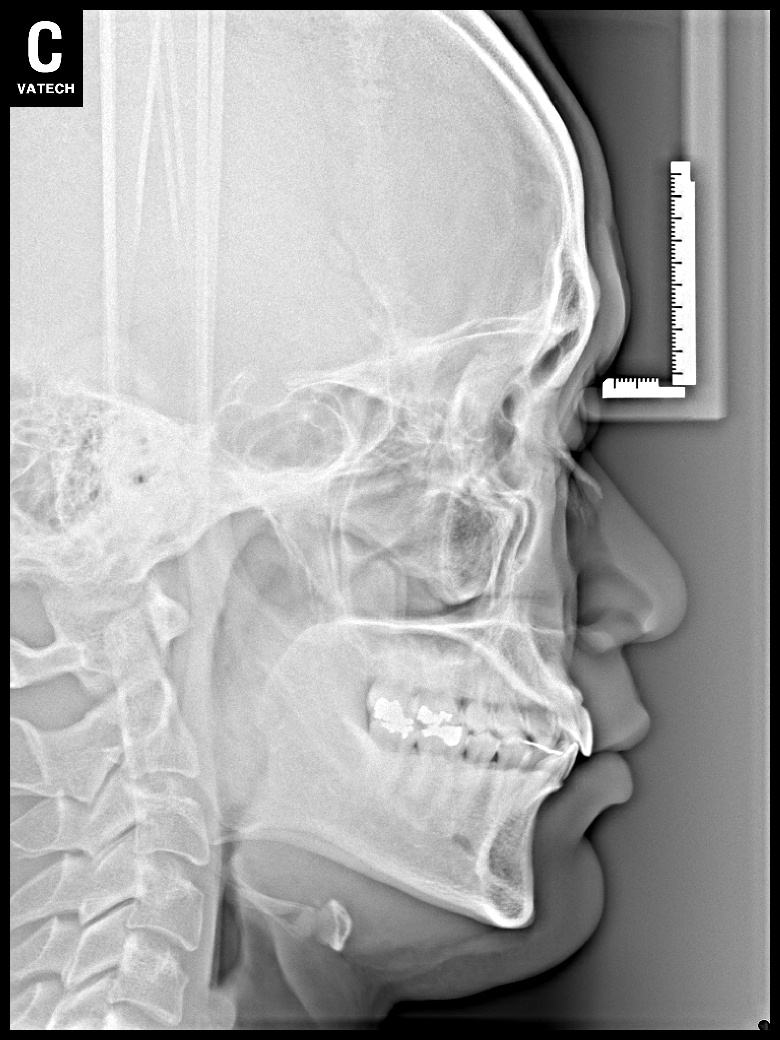

치료 후 사진입니다.